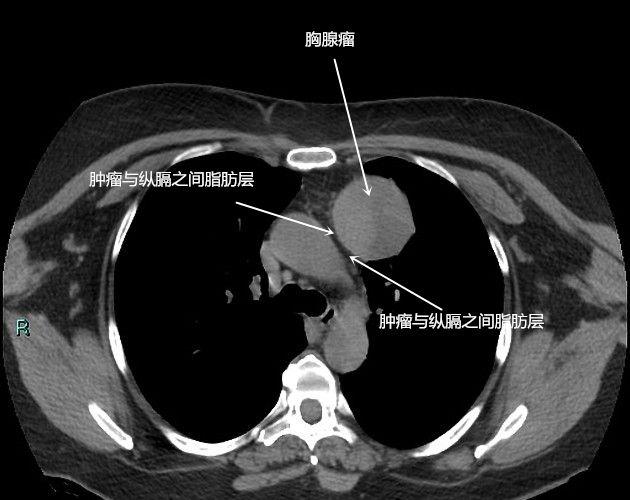

(6)纵膈

整个胸部可以分为胸廓、双肺和纵膈。除了气管、食管、大血管和心脏之外,胸部CT还可以发现纵膈里面有没有其他的问题,例如胸腺瘤,胸骨后甲状腺肿,畸胎瘤,皮样囊肿,神经节细胞瘤等等。

胸腺瘤